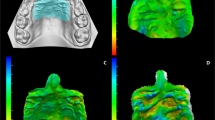

Table 2 presents the displacement amounts in the X-, Y-, and Z-axis directions at points N, Z, ANT, TPS-M, and TPS-L. A positive value along the X-axis indicates movement in the buccal direction, a positive value along the Y-axis indicates movement in the anterior direction, and a positive value along the Z-axis indicates upward movement. In all models, the X-axis values were positive, while the Y-axis and Z-axis values were negative. This means that all points experienced movement in the buccal, posterior, and downward directions. The largest variation in displacement values along the X-axis direction occurred when the expansion screw was activated. Model A, which had the smallest change in molar axis (Table 1), exhibited the smallest displacement amounts at each point (Table 2). Comparing Models C to F and Models G to J as grouped, there was a notable difference in the ANT point, with greater lateral expansion observed in Models C to F where the miniscrews were relatively anteriorly located. The expansion of the TPS-M and TPS-L points was almost identical in both groups. The ratios of ANT/TPS-M and ANT/TPS-L are provided in Table 2, with the largest ratio found in Model C and the smallest ratio in Model I. The displacement amounts and ratios are depicted in Figs. 1 and 2, respectively.

The geometric information of a human skull was imported into visual mesh software (version 7.0; ESI Group, Paris, France) to create a tetrahedral finite element (FE) mesh. The model included the maxilla, zygomatic bone, nasal bone, alveolar bone, teeth, and periodontal ligament. The skull model was generated using CT data from an adult male cadaver. To simulate the tissue and bone-borne palatal expander used in clinical practice, a virtual expander was created. It consisted of six miniscrews with a diameter of 1.6 mm and a length of 8.0 mm. The choice of 8.0 mm in length considered the thickness of the palatal mucosa. Bicortical positioning was not necessary as the miniscrews were placed on the palatal slope. The mesh size for the FE model was set at 2.0 mm, except for the area around the miniscrew, which was set at 0.2 mm to capture finer details (Fig. 4). The bone, teeth, and periodontal ligament structures were considered homogenous and isotropic. To replicate the opening pattern of the suture, the midpalatal and nasofrontal sutures were programmed to exhibit elastoplastic behavior. The modulus of elasticity and Poisson's ratio for each structure are provided in Table 3.

To observe detailed changes in the nasomaxillary complex and nasofrontal suture, five specific landmarks were included in the analysis. These landmarks, as depicted in Fig. 6, are as follows:

ANT: A 2 mm lateral point from the midpalatal suture on the line connecting the bilateral upper canines.

TPS-M: A 2 mm lateral point from the midpalatal suture on the transverse palatal suture.

TPS-L: The most lateral point of the transverse part on the transverse palatal suture.

These landmarks were selected to capture specific locations and provide a comprehensive evaluation of the changes in the anterior and posterior parts of the palate and the nasomaxillary complex. The ratios of ANT to TPS-M and ANT to TPS-L were calculated to compare the expansion patterns between the anterior and posterior parts of the palate, respectively.